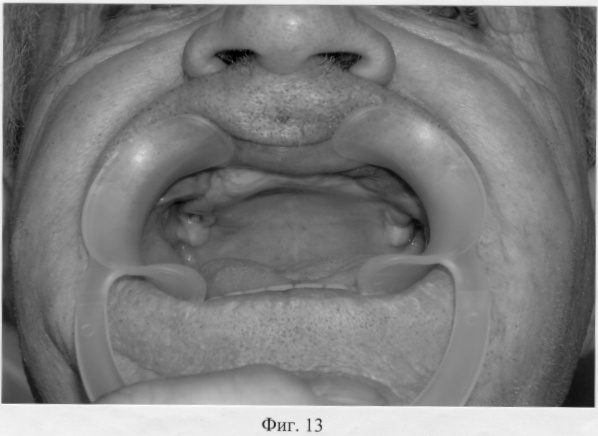

На фиг.13 – состояние полости рта больного Т. до ортопедического лечения.